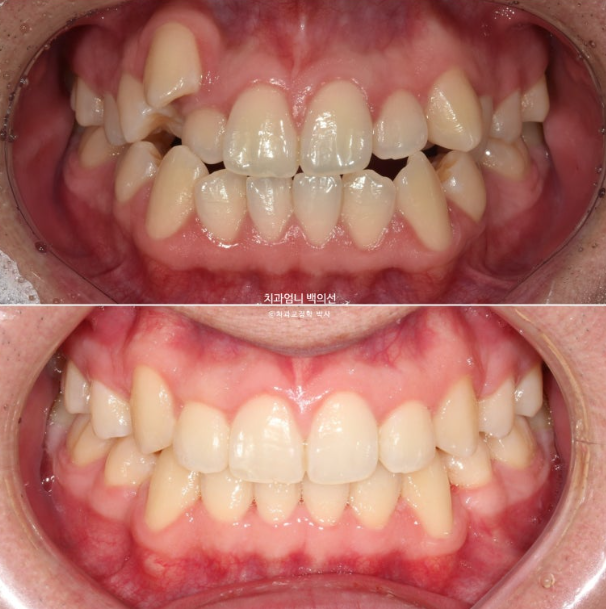

2022년 가을, 덧니 교정을 위해 오신 환자분입니다.

2022.09

송곳니 덧니가 심합니다. high canine 하이캐나인 이라고 합니다.

덧니가 심해서 작은어금니 4개 발치가 불가피한 상황입니다.

약간의 입술돌출도 함께 해소하기로 했습니다.

이제 전 후 비교 보겠습니다.

22.09~25.04

재제작은 총 2회 하였으며 치료기간은 2년 6개월 입니다. 중간중간 장치제작기간을 제외하면 실제 치료기간은 2년 2개월 입니다.